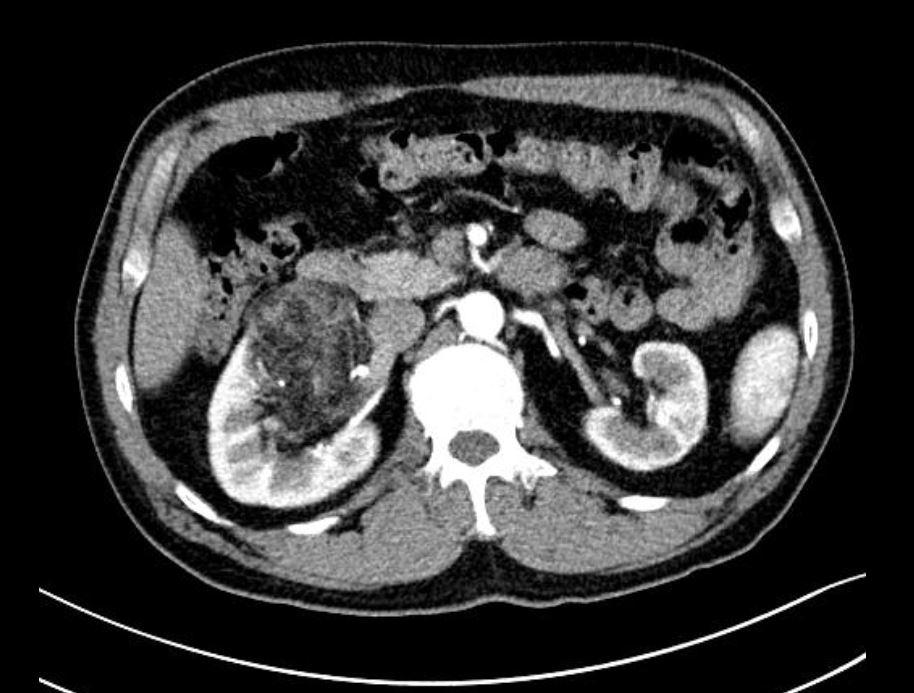

机器人手术的优势,对于经历过手术的患者来说感触最深。51岁的患者郑先生7年前体检发现肾错构瘤,复查发现错构瘤呈进行性增大。来到市一南部复查后,发现他的右肾中部有一个很大的肿瘤,更加不巧的是,这个肿瘤“刚好”长在肾门部,一支重要的动脉穿过肿瘤,被包裹在其中。“一旦术中伤及动脉,致使整条主干断裂,整个肾脏将失去功能。”泌尿临床医学中心(南)执行主任许传亮教授表示。既要清除病灶,又要不伤害肾脏,机器人在精准性、安全性与功能保护三方面的优势,正好可以满足手术的要求。通过高自由度机械臂与三维高清成像系统,医生可以清晰辨识肿瘤边界与血管走行,在精准切除病灶的同时,最大限度保留正常肾实质,降低热缺血时间,保护肾脏功能。机械臂的震颤滤除功能则显著提升了缝合精度,减少了集合系统损伤与尿漏并发症。最终,郑先生的手术用时不到2小时,在未损伤重要动静脉的基础上,切除了全部错构瘤瘤体。